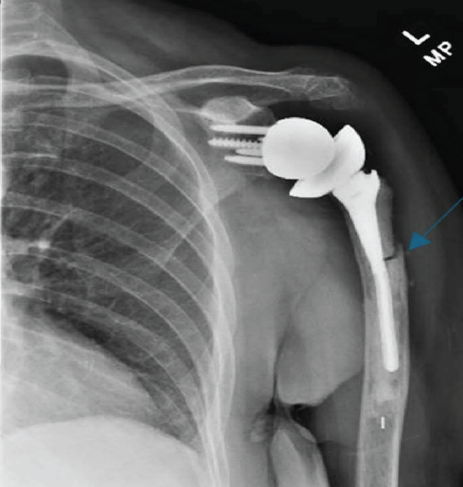

Transverse Periprosthetic Fracture With a Bent Stem Following Reverse Total Shoulder Arthroplasty – A Case Report

James H Padley , Emanuel-Youssef Dib , Alexander R Zhu , Eve R Glenn , Henry M Fox , Edward G McFarland

………………………………p.255-259